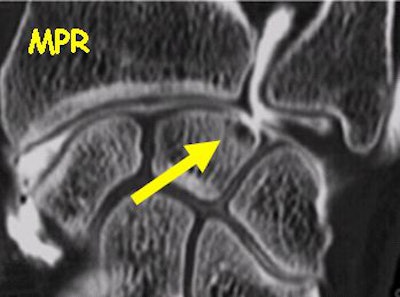

Direct and multiplanar reformatted views of wrist CT arthrography show nearly equivalent information for the depiction of ligament tears. Images courtesy of Dr. Sandrine Iochum, CHU Nancy, France.

![]() |